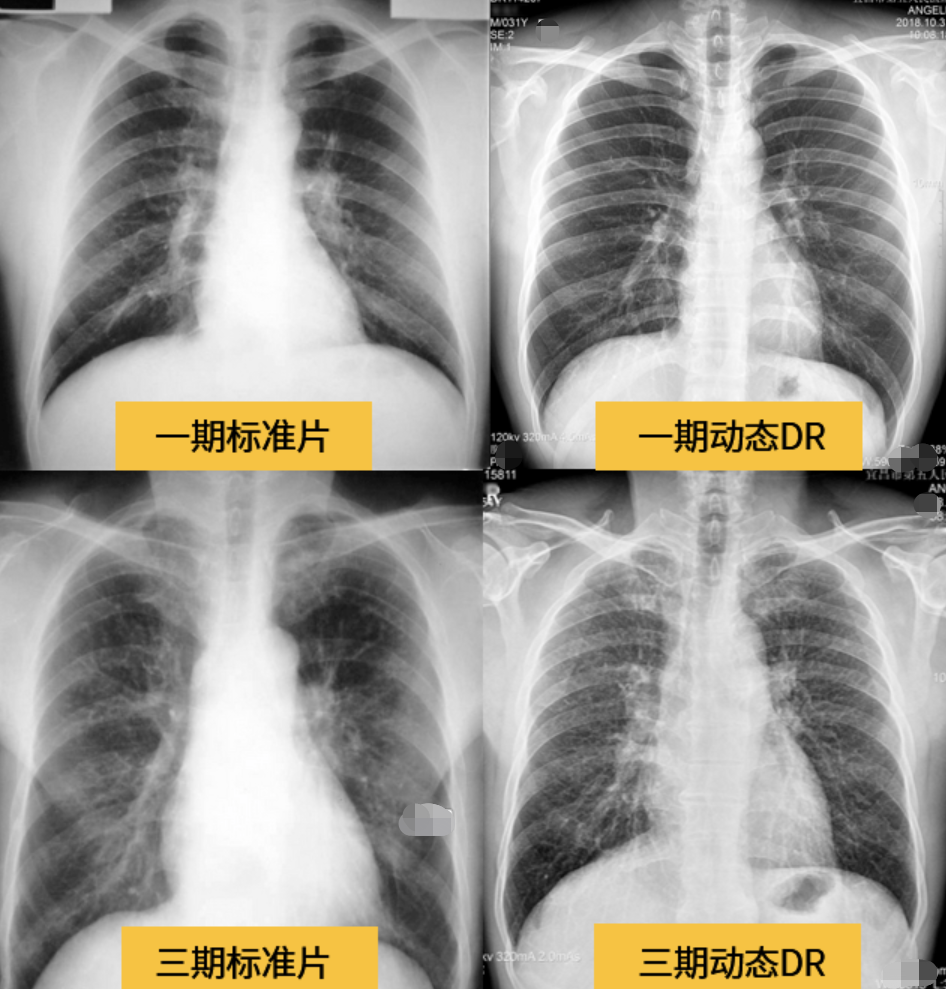

七喜醫(yī)療天鹿系列懸吊DR搭載高品質(zhì)動(dòng)態(tài)平板探測(cè)器,不僅滿足常規(guī)的數(shù)字化X線全身攝影需求,同時(shí)還擁有數(shù)字?jǐn)z影、數(shù)字透視、數(shù)字造影、全景拼接等多種功能,極大地拓展了X線檢查在臨床應(yīng)用范圍,為醫(yī)院臨床應(yīng)用帶來(lái)更多實(shí)用價(jià)值?;诎傥⑵桨宓母咔宄上瘢瑘D像清晰度與分辨率更高,可滿足不同檢查部位對(duì)細(xì)節(jié)成像的高品質(zhì)要求,在胸腹部、脊柱等復(fù)雜骨骼和軟組織的攝片上應(yīng)用,更便于觀察隱匿性病灶,精準(zhǔn)識(shí)別疑難病癥。

不同于靜態(tài)DR拍攝隱匿性病灶時(shí),由于組織重疊病灶難辨,耗費(fèi)時(shí)間更長(zhǎng)且易漏診、誤診,動(dòng)態(tài)懸吊DR可通過(guò)動(dòng)態(tài)實(shí)時(shí)連續(xù)成像,對(duì)于重疊部位病灶或者易被遮擋的病灶進(jìn)行多角度動(dòng)態(tài)觀察,毫秒級(jí)時(shí)間內(nèi)實(shí)現(xiàn)動(dòng)靜態(tài)轉(zhuǎn)換點(diǎn)片,快速、精準(zhǔn)完成攝片。比如隱匿性肋骨骨折,可在透視下觀察患者的呼、吸過(guò)程,避開(kāi)重疊影像,快速點(diǎn)片,保證檢查部位的病癥不被遺漏,實(shí)現(xiàn)精準(zhǔn)診斷。